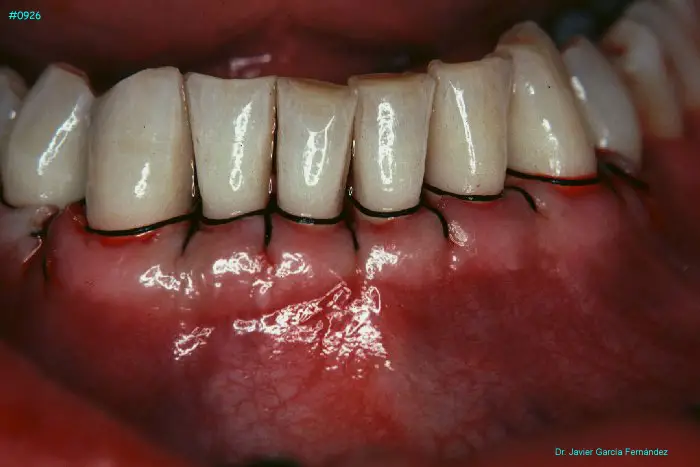

Atlas of Surgical Techniques in Periodontics. Chapter III. Atlas de Técnicas Quirúrgicas en Periodoncia